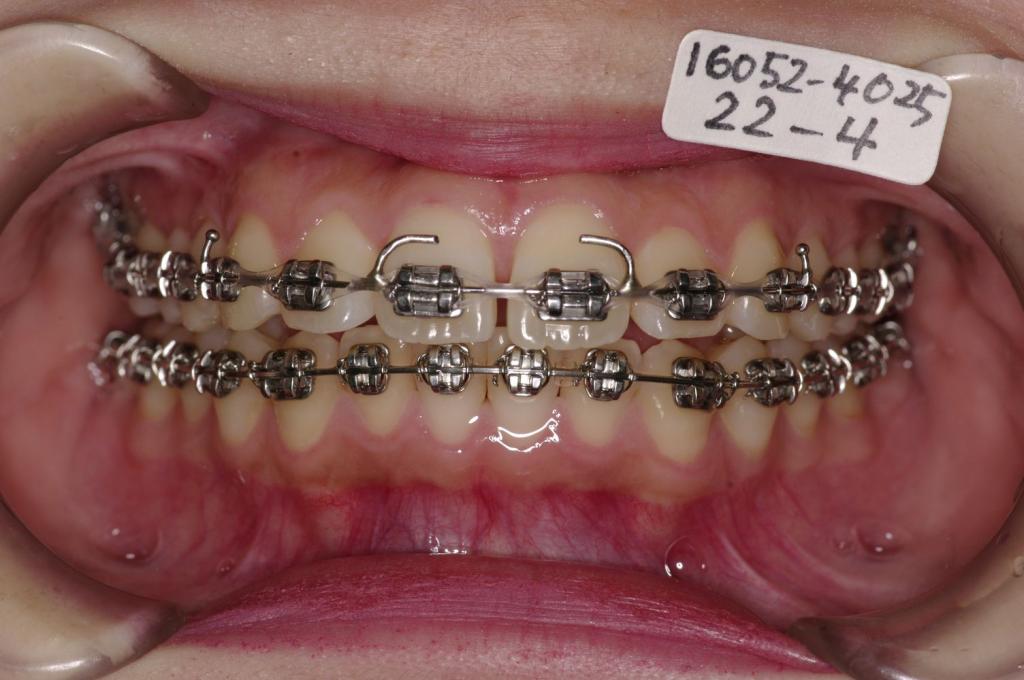

- 前歯、出っ歯・開咬の矯正治療

- 出っ歯

- 上下の前歯の間に舌を入れる癖がある場合には、歯の裏側にフックを付ける場合があります。その場合発音がしにくくなったり、食事の時に舌が痛かったりすることがあります。